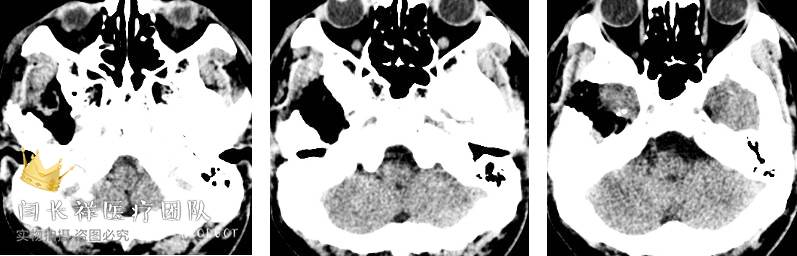

术前MRI轴位T1扫描示病灶呈等信号。

术前MRI轴位T2扫描示病灶侵及面神经膝段及中耳骨质。

术前MRI轴位T1增强示病灶显著不均匀强化。